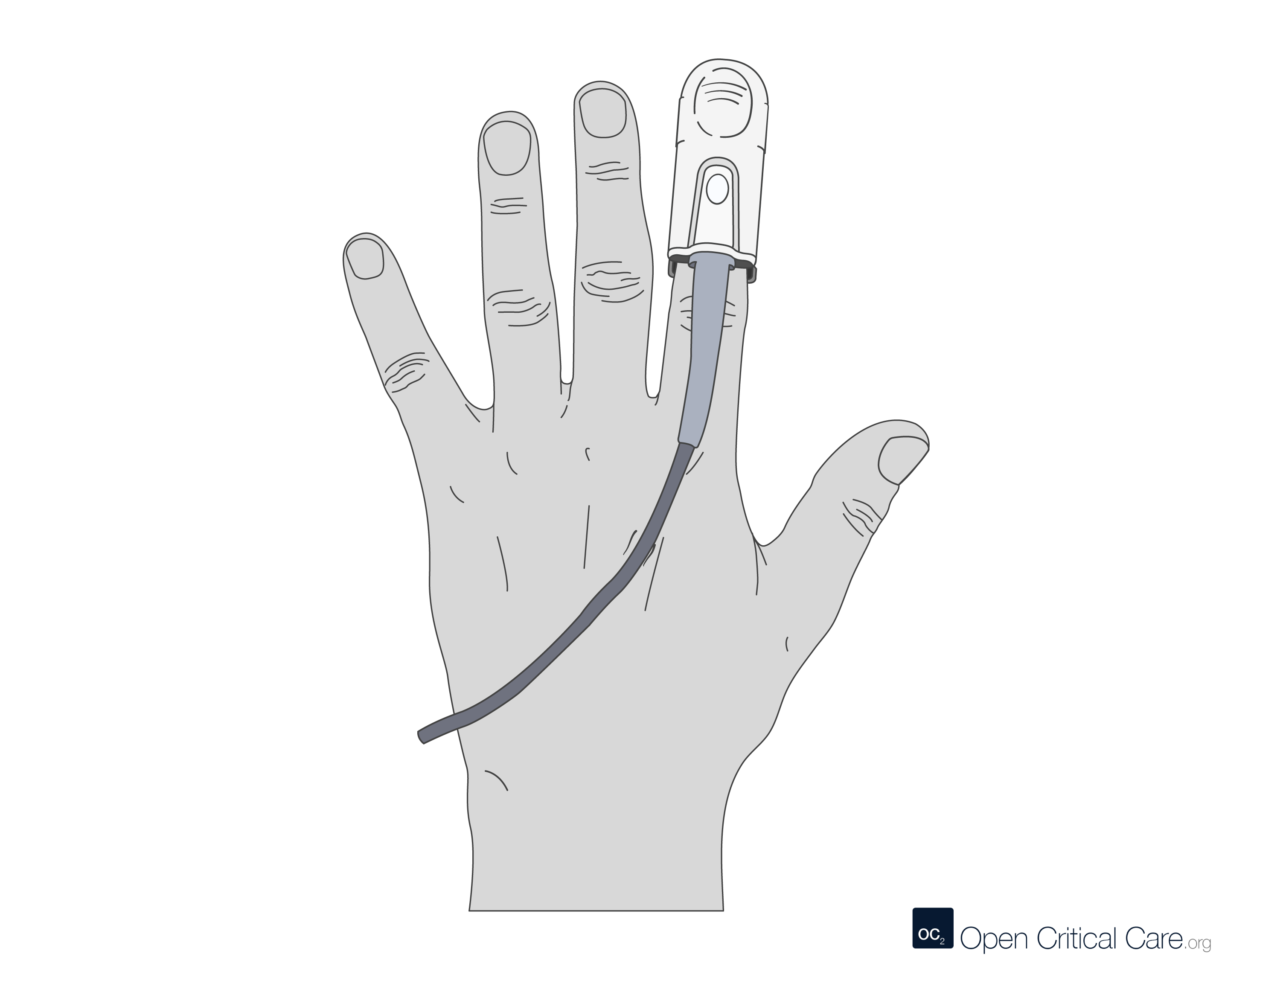

2 – Diagnostic Tools – Spirometry, Arterial Blood gas, Oximeter, Exercise Tolerance Testing, X-ray, Bronchoscopy, Culture and Sensitivity Tests, Sneezing Reflex, Coughing Reflex,

- High flow nasal cannulae – consists of wider – bore prongs and offers humidification and titration of oxygen concentrations to be delivered.